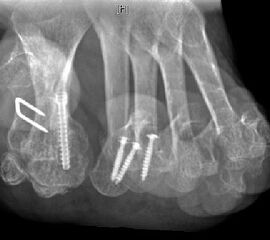

11"> Der Hallux varus Winkel  <a class=11" title="Der Hallux varus Winkel 11" srcset="/assets/images/2/4-vk3bypbg5s5x7zc.jpg 1x, /assets/images/3/4-aax2sd1hrpnrvrb.jpg 1.452x" width="270" height="240" loading="lazy">

Abbildung 3

Die bildgebende Diagnostik hilft bei der Klärung der Ätiologie und des Ausmaßes der Fehlstellung. Hierzu sind Röntgen­aufnahmen im Stand in mindestens zwei Ebenen unter Belastung des Fußes erforderlich. Mit Hilfe der belasteten Röntgenaufnahmen wird der Hallux-varus-Winkel, d. h. den Winkel zwischen der Achse der Grundphalanx der Großzehe und der Achse des ersten Mittelfußknochens bestimmt, sowie etwaige Rotationsfehlstellungen des 1. Strahls verifiziert. Eventuelle knöcherne Fehlanlagen bei kongenitalen Deformitäten können hierdurch ebenfalls verifiziert werden.

Weitere Beurteilungskriterien sind:

• degenerative Veränderungen des MTP I

• Kongruenz des MTP I- Gelenkes

• Form und Stellung des Mittelfußköpfchens I

• Ausprägung der Pseudoexostose.

• PASA-Winkel, d. h. der periphere Artikulationswinkel des Großzehengrundgelenkes.

Zur Klärung der Ätiologie wird der intermetatarsale Winkel zwischen Os metatarsale I und II bestimmt. Ist dieser kleiner als 5° oder gar negativ, ist eine Varusstellung der Großzehe oft die Folge.

Am Röntgenbild des belasteten Fußes bestimmt man die Lage der Sesambeine zum 1. Mittelfußköpfchen.

Anhand der Röntgenaufnahme lassen sich die Folgen einer eventuellen Voroperation bestimmen, wie z. B. die Stellung des ersten Mittelfußköpfchens, des ersten Metatarsale nach Korrekturen der Achse bei einer Hallux-valgus-Operation. Mitunter bestehen Nekrosen des Mittelfußköpfchens oder eine übermässige Resektionen der Pseudoexostose. Auch die Länge des 1. Metatarsale kann von Interesse sein, z. B. nach einer Lapidusarthrodese (Johnson 1994).